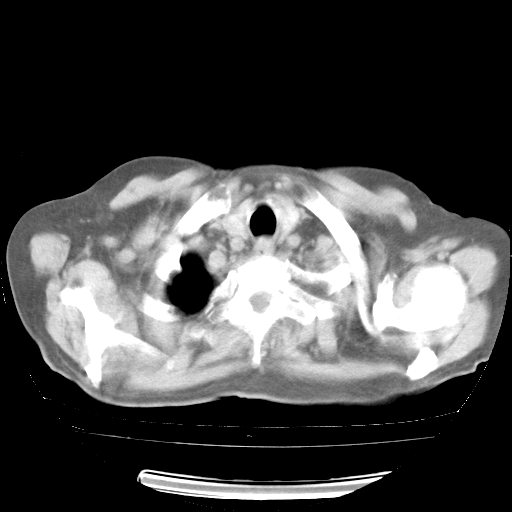

4月28日肺部CT——再次出现类似去年5月9日——透光度降低,“间质性”改变。

4月28日肺部CT——再次出现类似去年5月9日——磨玻璃样、间有“粟粒样”改变。